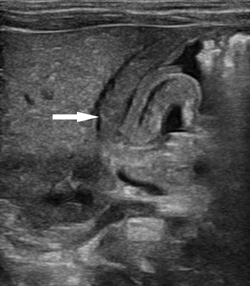

患儿女,33天,足月儿,因“反复严重呕吐30+天”于我院小儿外科门诊就诊,遂建议超声检查排除“先天性肥厚性幽门狭窄”。超声所见:十二指肠呈空虚状态。幽门壁肌层最厚约4.4mm,幽门最大横径约14mm,幽门管长约19mm(图1-3),幽门管腔变窄,胃内查见液性及稍强回声潴留物,胃内容物通过幽门管受阻(图4)。超声诊断为“先天性肥厚性幽门狭窄”。遂入院手术治疗,术中及术后病理证实为CHPS。

图1:幽门纵断